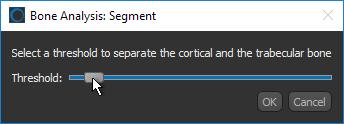

If you selected the Kohler method, use the slider to select a threshold to separate the cortical and trabecular bone.